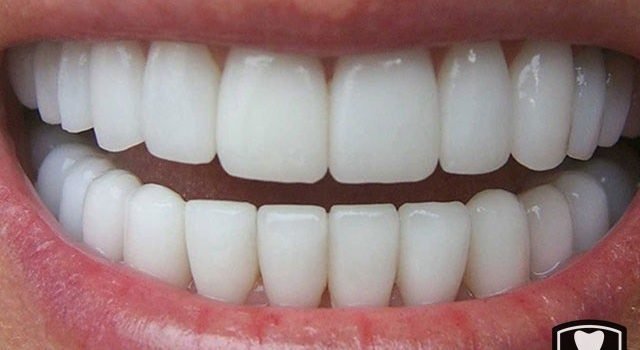

Lazerle implant

Lazerle implant diş etine dikiş atılmadan çok kısa bir sürede tamamlanan modern implant tedavi uygulama yöntemidir. Zamandan tasarruf sağlar.